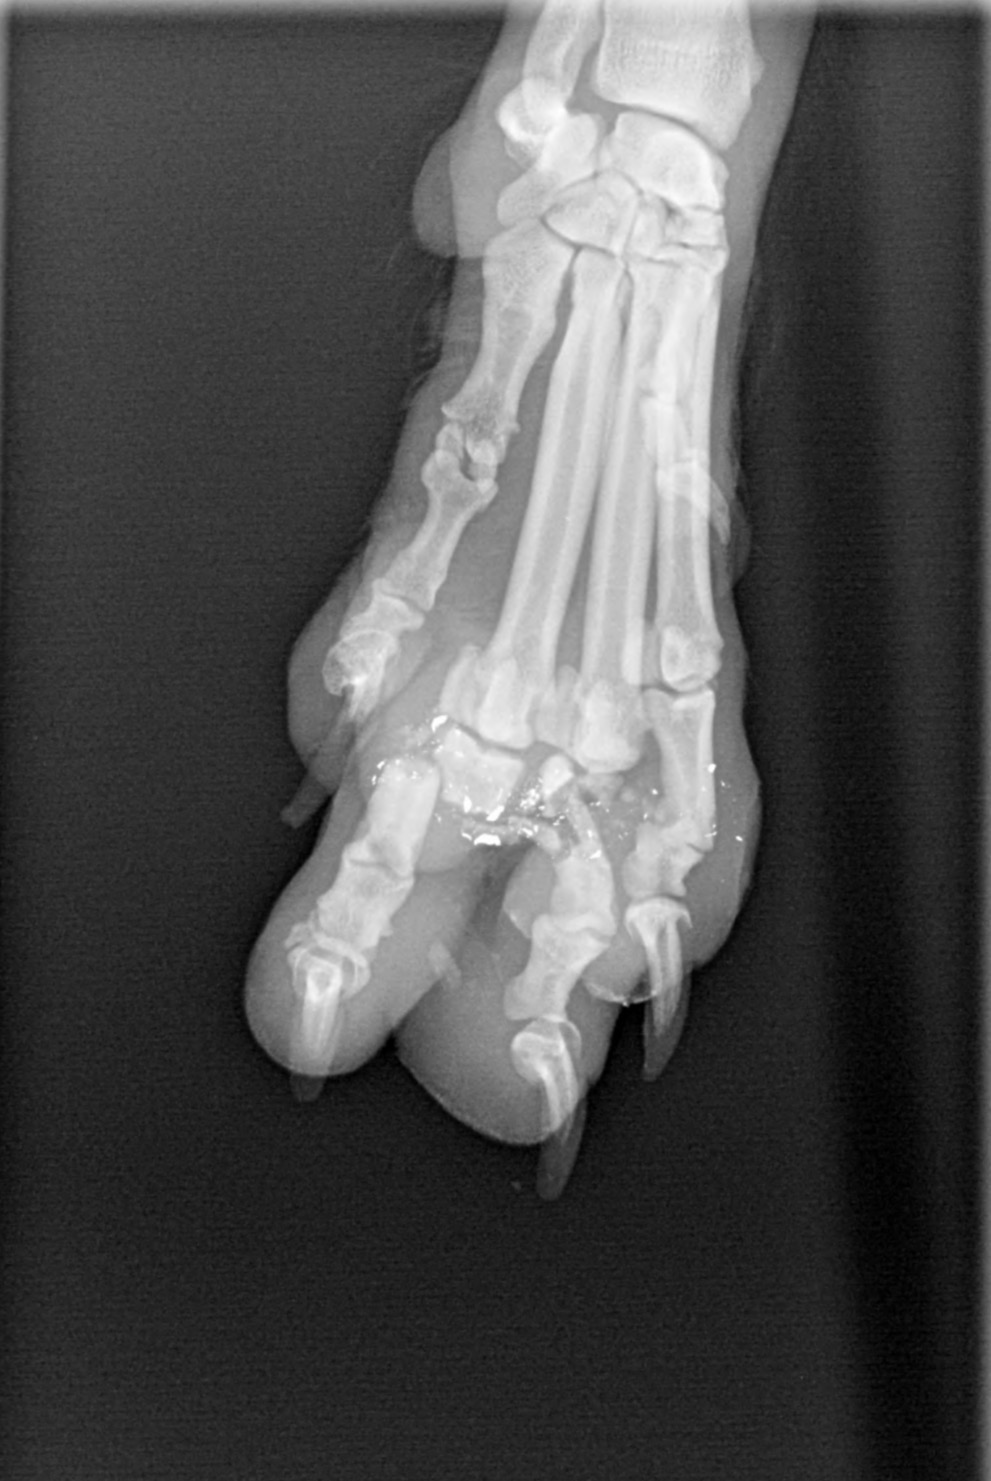

Hi! My name is Trinity Fleming :) I have recently rescued a dog I named Scruffy from the streets!! Unfortunately, his entire right front foot is broken due to a gunshot wound and I am trying to afford medical help to heal his wounds. Please consider donating or helping spread the word so I can get Scruffy the help he very much needs to save his foot! Thank you in advance!!